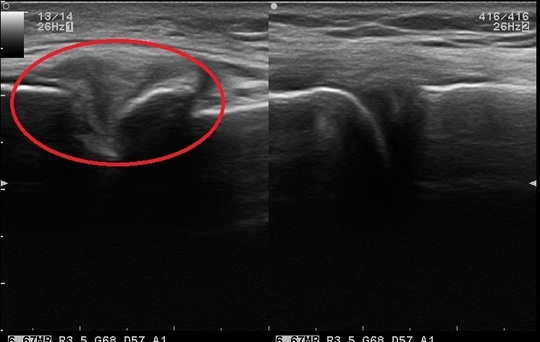

60歳 男性 左膝関節の痛み(変形性膝関節症)

当院来院時

患者本人の膝関節

スタッフの膝

整形外科にて通院・リハビリをするも膝関節の痛み変わらず当院に来院。

現在、歩いての痛み、階段の上り下りでの痛み。しゃがみ込みの痛みあり。

エコー観察下にて、膝関節の変形・軽度の水腫ありと判断。

72歳 男性 右膝関節の痛み(変形性膝関節症)

左:患者の膝

右:スタッフの膝

整形外科にて手術適応と言われるも、保存療法(手術しない)を選択。

当院のエコー観察下にて軟骨の変性・関節変形を確認。